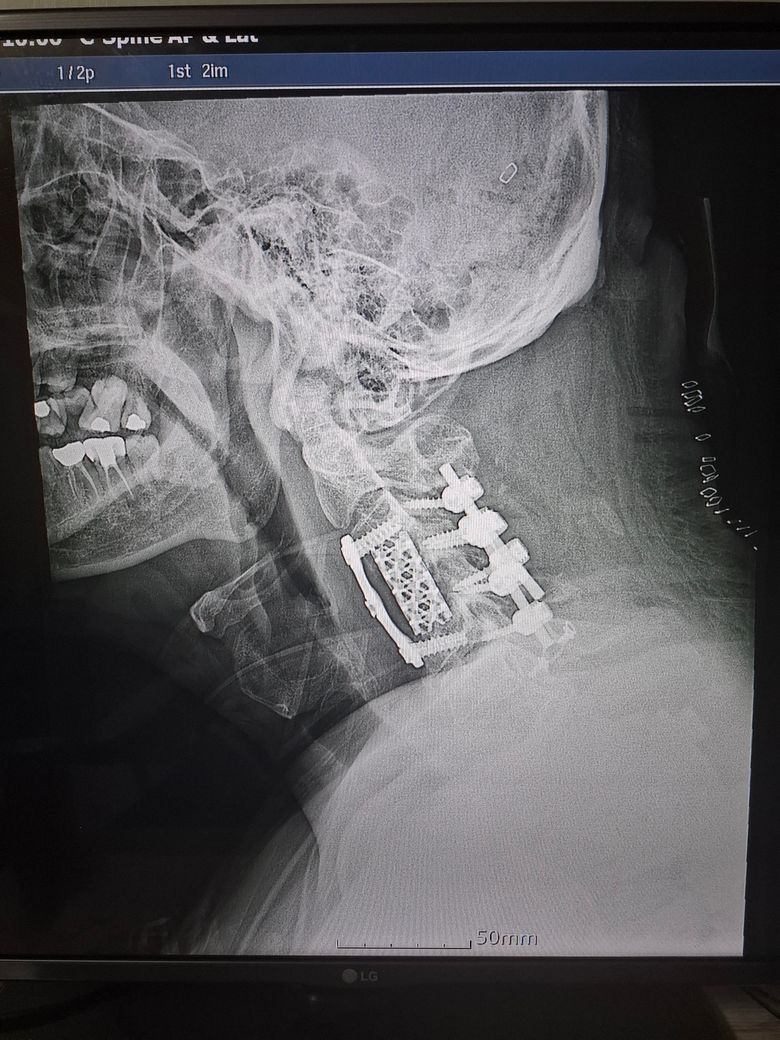

경추 유합 수술후에 통증에 좋은 약 추천

수술후 이런 상태인데요

목 뒤쪽이 너무 아프네요

통증잡는 좋은 약 있을까요?

현재 뉴론틴 먹고 있긴한데 하루 3번을 먹어야 될까요?